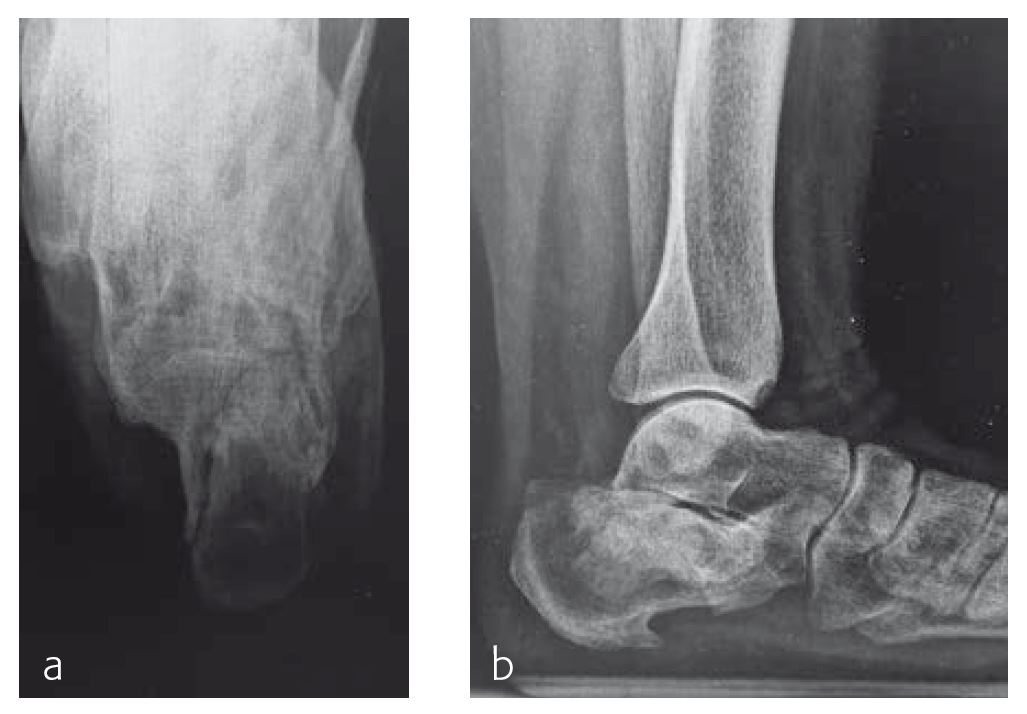

Case 1: Ladder fall

A 58-year-old woman (Fig 1), who had fallen from a ladder 9 weeks earlier, had indications of a malunited fracture and was referred to the clinic by a family physician.

The malunion had to be treated with an osteotomy to reconstruct the joint and regain normal function. The osteotomy was fixed with the VA Locking Calcaneal Plate (Figs 2 and 3).